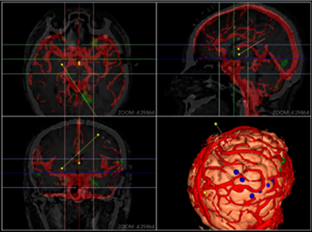

同方鼎欣專業(yè)影像產(chǎn)品群是直接面向神經(jīng)外科、骨科、血管分析等臨床科室的輔助診療、手術計劃、分析的解決方案,系統(tǒng)整合了醫(yī)療影像的導入、二維閱片、三維重建、序列配準融合、自動分割、自動計算、手術計劃等一系列功能。充分滿足了臨床科室的專業(yè)需求,提供了完整、強大、可靠、方便的工具平臺。

三維體繪制重建(VR)、三維面繪制重建(SR);

融合(Fusion)、融合結(jié)果三維重建;

神經(jīng)外科手術規(guī)劃模塊;